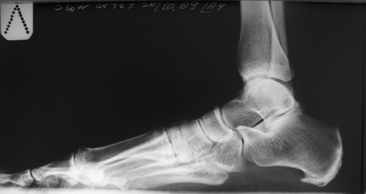

Как правильно заметил Михаил Васильев, нехватает некоторых мелочей. Пациентка В., возраст 45 лет. Вес 64,5 кг. Рост 168 см.

Мы так же как и доктор Кулешов установили диагноз стресс перелома или болезнь Дойчлендера. Пациента сейчас находится в гипсовой иммобилизации сроком уже 3 недели. До обращения к нам, пациентка лечилась по месту жительства без какой либо фиксации, нагружая ногу полностью.

Что касается дальнейшей тактики лечения... У пациентки только один негативный элемент - это болевой синдром, при нагрузки на конечность.Буквально пройти 200 - 250 метров это огромная проблема...

Высылаю ещё Ро - граммы. Мне кажется должно получиться.